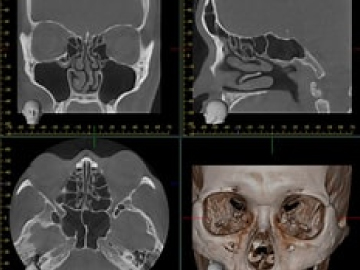

医療機器CTや内視鏡など当院のおもな検査機器についてご紹介します。